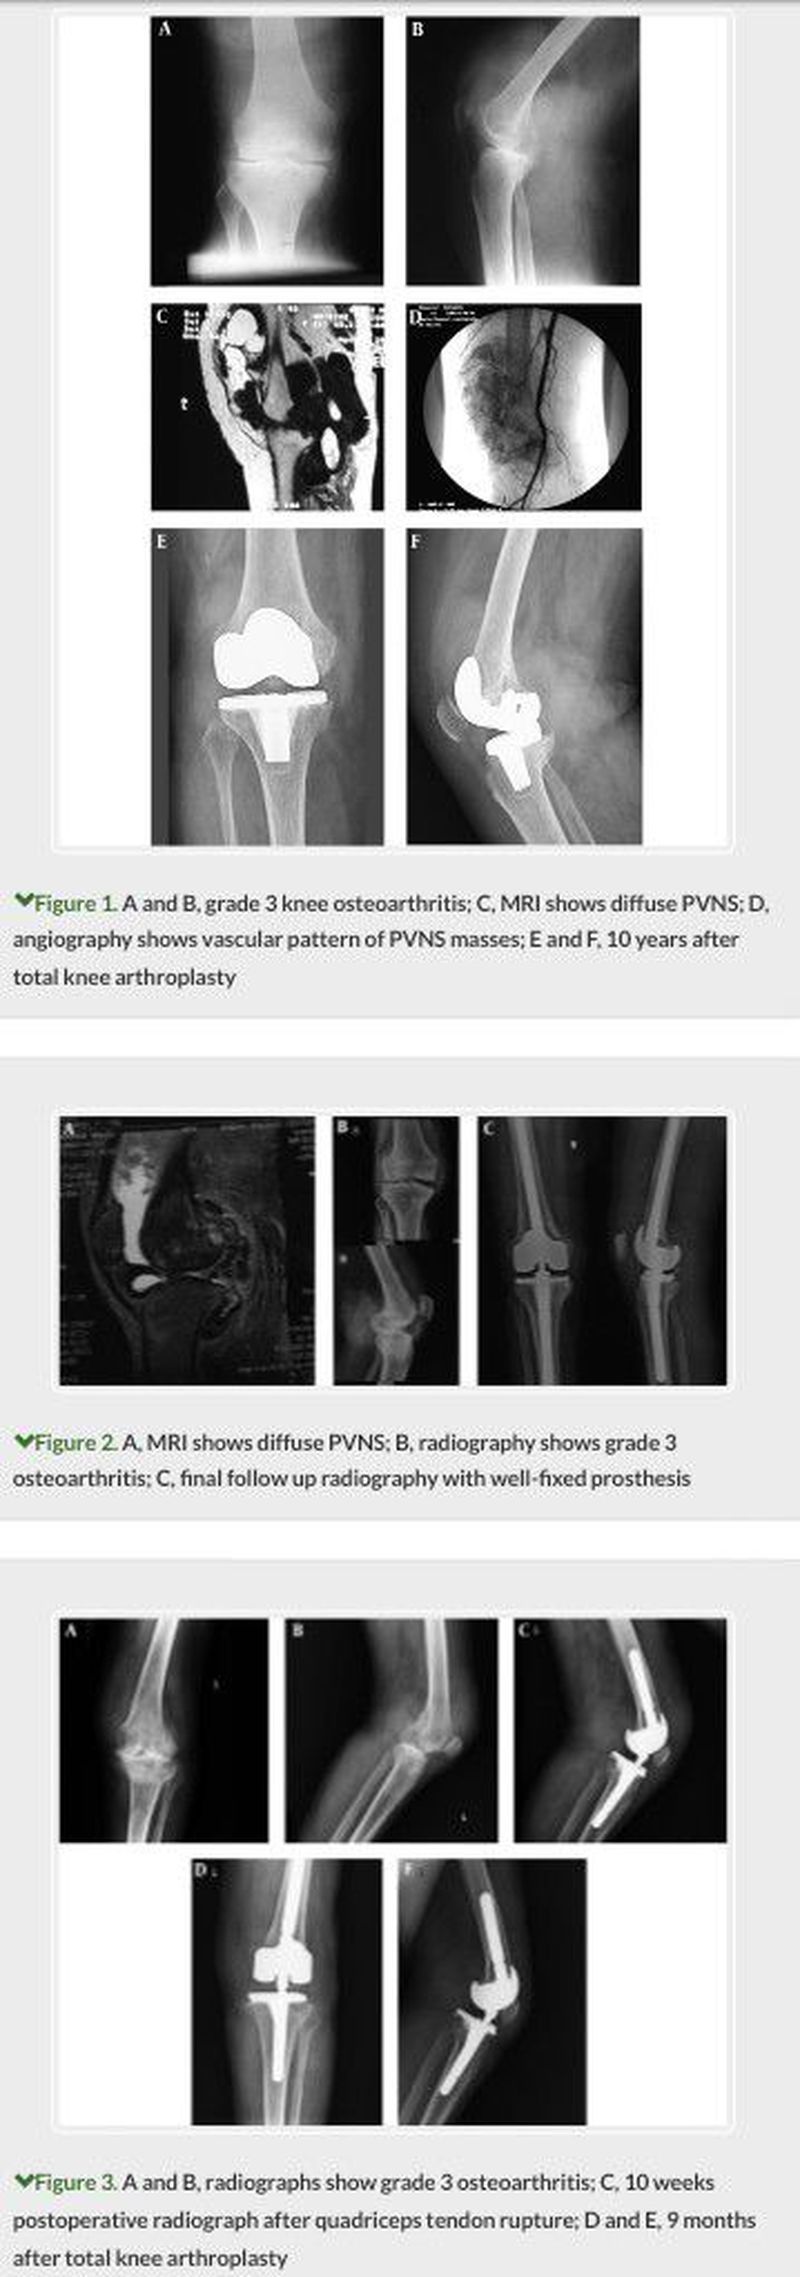

A 61-year-old woman was referred to our clinic because of right knee pain and swelling. She had a history of painful swelling of the knee for about 8 years and was treated by open debridement for 7 years and aspiration and corticosteroid injection 6 years before admission in another center. At presentation, the right knee had obvious swelling with large all-around palpable mass with 0 - 100 ranges of motion (ROM). She had no history of trauma, rheumatoid or hematologic disorder and diabetes mellitus. In AP/lateral X-rays grade 3 osteoarthritis, according to Kellgren and Lawrence, radiographic grading system (5) and huge soft tissue mass shadow in suprapatellar pouch and posterior popliteal area was seen (Figures 1a and 1b). An MRI showed the extent of the mass and was in favor of PVNS (Figure 1c). Because of weak tibialis posterior (TP), pulse angiography was performed, which confirmed TP occlusion and mass blood perfusion from genicular branches (Figure 1d). Arthroscopic biopsy confirmed the diagnosis of PVNS. Surgery was done in 2 stages. In the first stage, 3 months after the biopsy, in prone position and lazy S popliteal incision the posterior mass excised. One month later, in supine position, with standard anterior midline incision, anterior mass excised and posterior stabilized total knee arthroplasty (TKA) with LPS prosthesis (Zimmer Biomet, Warsaw, Indiana, USA) was performed. At the 10 year follow-up she is painless without recurrence of disease and the prosthesis is stable (Figures 1e and 1f). According to the knee injury and osteoarthritis outcome score (KOOS) (6) the functional result is excellent. A 63-year-old man who had a diffuse form of PVNS and history of 2 time open right knee arthrotomy and synovectomy with 3 incisions in posterior, medial, and anterior surface of the knee in 2002 and 2003 in another center. The ultrasound showed 2 40 × 26 and 45 × 30 millimeters masses in popliteal space of knee. MRI confirmed the masses (Figure 2a). On admission he had grade 3 osteoarthritis, according to Kellgren and Lawrence radiographic grading system (Figure 2b). ROM was 60 degrees with 20 degrees flexion contracture. Due to the severe disabling pain, total knee replacement with LCCK prosthesis (Zimmer Biomet, Warsaw, Indiana, USA) was performed. At the time of TKA 2 masses and synovium were excised. One year after TKA he has no pain or swelling. ROM is 110 degrees without flexion contracture. Prosthesis is well fixed (Figure 2c). According to knee injury and osteoarthritis outcome score (KOOS) the functional result is excellent. An 80-year-old man with history of a car to pedestrian accident 8 years before referring to our clinic without history of fracture or soft tissue injury of his left knee. His main complaint was his left knee pain and swelling. ROM was 90 degrees with 10 degrees flexion contracture. In the X-ray, grade 3 osteoarthritis, according to Kellgren and Lawrence radiographic grading system, and diffuse soft tissue mass was seen (Figures 3a and 3b). The MRI revealed characteristic findings of diffuse PVNS. Arthroscopic biopsy was performed and confirmed the diagnosis. Two months later, with anterior standard medial parapatellar approach, total synovectomy and rotating hinged TKA (Zimmer Biomet, Warsaw, Indiana, USA) was performed. One-week after the operation, the patient returned to the operating room, the hematoma was evacuated and hemovac drain inserted then discharged without complication 1 week later. Ten weeks after TKA, the patient suffered simple falling down and quadriceps femoris tendon ruptured (Figure 3c). Direct repair of quadriceps femoris tendon and augmentation with no 5 non-absorbable suture performed. At the last visit, 9 months after index operation, the patient had 30-degree extension lag with 0 - 110 passive ROM. Prosthesis is stable without recurrence of disease (Figures 3d and 3e). According to knee injury and osteoarthritis outcome score (KOOS) Functional result is fair.